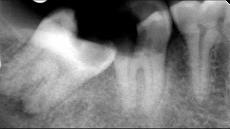

- 多项选择题关于阻生牙阻力来源正确的是 ( )

A、阻力来源于邻牙

B、阻力来源于骨组织

C、阻力来源于牙龈

D、阻力来源于咀嚼肌

E、阻力来源于对

牙